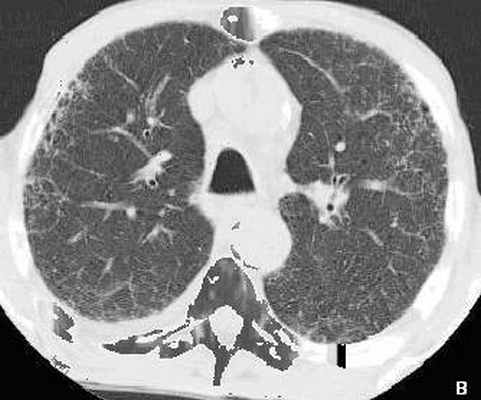

Рис. 3(А, Б). КТ грудной клетки больного Г., 72 лет. Малодифференцированный рак на фоне обычной интерстициальной пневмонии (морфологическая верификация).

А - аксиальный срез на уровне верхних долей легких, выявлены участки диффузного снижения пневматизации по типу «матового стекла», утолщение внутридолькового интерстиция (белая стрелка), в переднем сегменте верхней доли слева на границе интерстициальных изменений и нормальной легочной ткани выявлена субплевральная консолидация неправильной округлой формы (черная стрелка). Б - МПР в коронарной проекции на уровне консолидации. Рассчитанное значение 3 D – коэффициента составило 1.65 ( D max axial / D min cor = А/В = 1.65). Проведена морфологическая верификация консолидации под контролем КТ-скопии – диагностирован малодифференцированный рак.